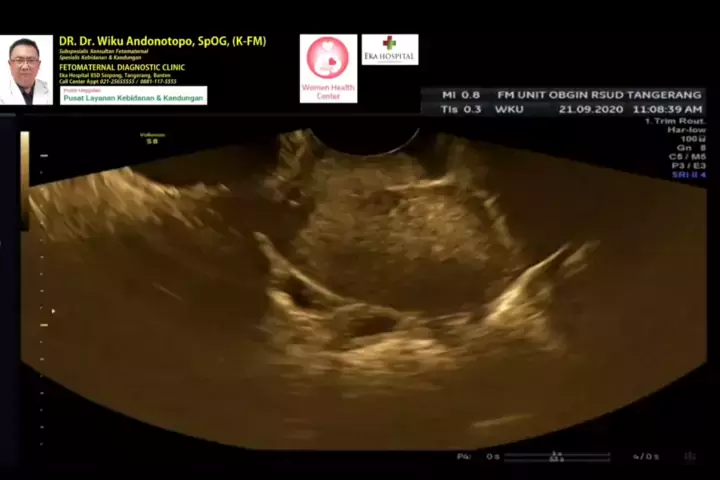

Kehamilan Ektopik... #ectopicpregnancy #kehamilanektopik #wikuandonotopodr